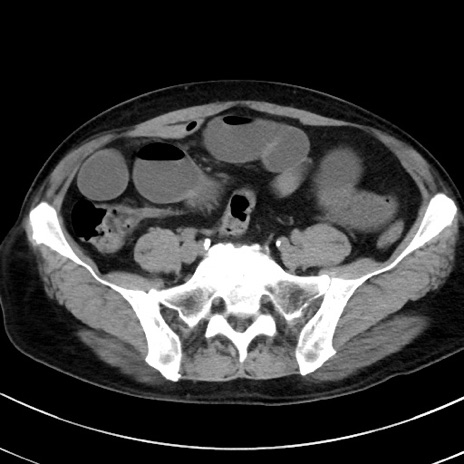

症例38(横断像)

【症例】70歳代 男性

【主訴】腹痛・嘔吐

【現病歴】昨晩より、嘔吐・腹痛あり。今朝になっても嘔吐あり。来院。

【既往歴】心臓バイパス手術、開腹胆摘、腸閉塞

【身体所見】BP 107/71mmHg、HR 116/min、腹部:平坦、軟、下腹部に軽度圧痛あり。反跳痛なし。

【データ】WBC 15100、CRP 0.32